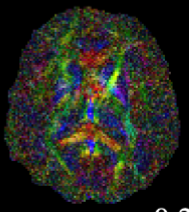

Inverse Problems in Neuroscience: Susceptibility Tensor Imaging